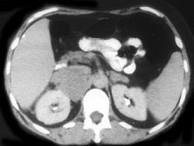

问题 男,65岁,腋下触及肿大包块,全身浅表淋巴结肿大,请结合所提供图像,选择最佳答案()

选项 A.双侧肾上腺腺瘤 B.双侧肾上腺增生 C.双侧肾上腺淋巴瘤 D.双侧肾上腺转移瘤 E.肾上腺癌

答案 C